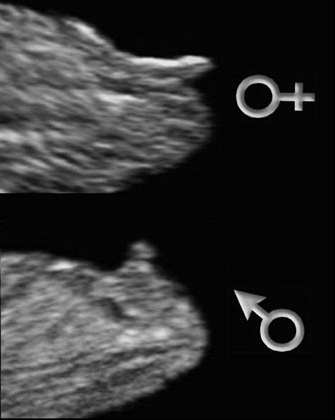

Se tromper de sexe à léchographie. La relation du 24 septembre nest donc pas fécondante il est impossible davoir de telles différences. Léchographie du premier trimestre les méthodes pour reconnaître le sexe du bébé Déchiffrer léchographie.

Pour ma 2nde. Pour une échographie vésicale il faut avoir la vessie pleine afin quelle apparaisse clairement sur lécran. On peut se tromper de sexe à la première échographie mais à la seconde ou la dernière cela relève de lexceptionnel.

Lors de la seconde échographie il est possible de voir le sexe encore faut-il que le bébé se présente dans la bonne position. Pour mon 1er. Le tubercule sest transformé en clitoris ou en pénis.